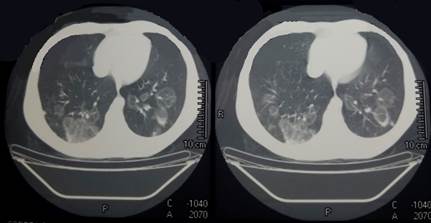

De la tomografía (TC) realizada destacamos a nivel del macizo facial engrosamiento mucoso del seno maxilar derecho; a nivel de cuello engrosamiento de la pared lateral izquierda de la orofaringe con adenomegalias yugulo-carotídeas, submaxilares bilaterales y cervicales posteriores, mayores a izquierda con centro hipodenso de aspecto necrótico; en tórax presentaba múltiples opacidades en vidrio deslustrado, redondeadas, de distribución bilateral y difusa, rodeadas por consolidación en forma de anillo, configurando el signo del “halo invertido”; a nivel de abdomen presentaba hepatomegalia (Figura 3).

En cuanto a los hallazgos radiológicos se pueden observar en la radiografía de tórax infiltrados intersticiales y alveolares mixtos, que suelen ser perihiliares, bilaterales y simétricos con una participación predominantemente menor en el campo pulmonar. Las imágenes más frecuentes en la TC de tórax son atenuaciones de vidrio esmerilado, consolidaciones, nódulos, masas, cavidades y engrosamiento septal o interlobular; el signo de halo invertido puede estar presente. La afectación pulmonar prolongada puede provocar secuelas graves, como fibrosis, cavidades y enfisema 3). En este paciente se observaron los infiltrados intersticiales bilaterales y la imagen en halo invertido en la TC de tórax.